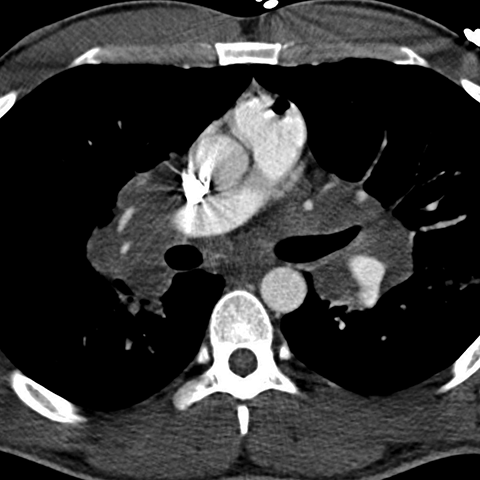

Hilar and Paratracheal Nodes in Sarcoidosis [3 of 3]